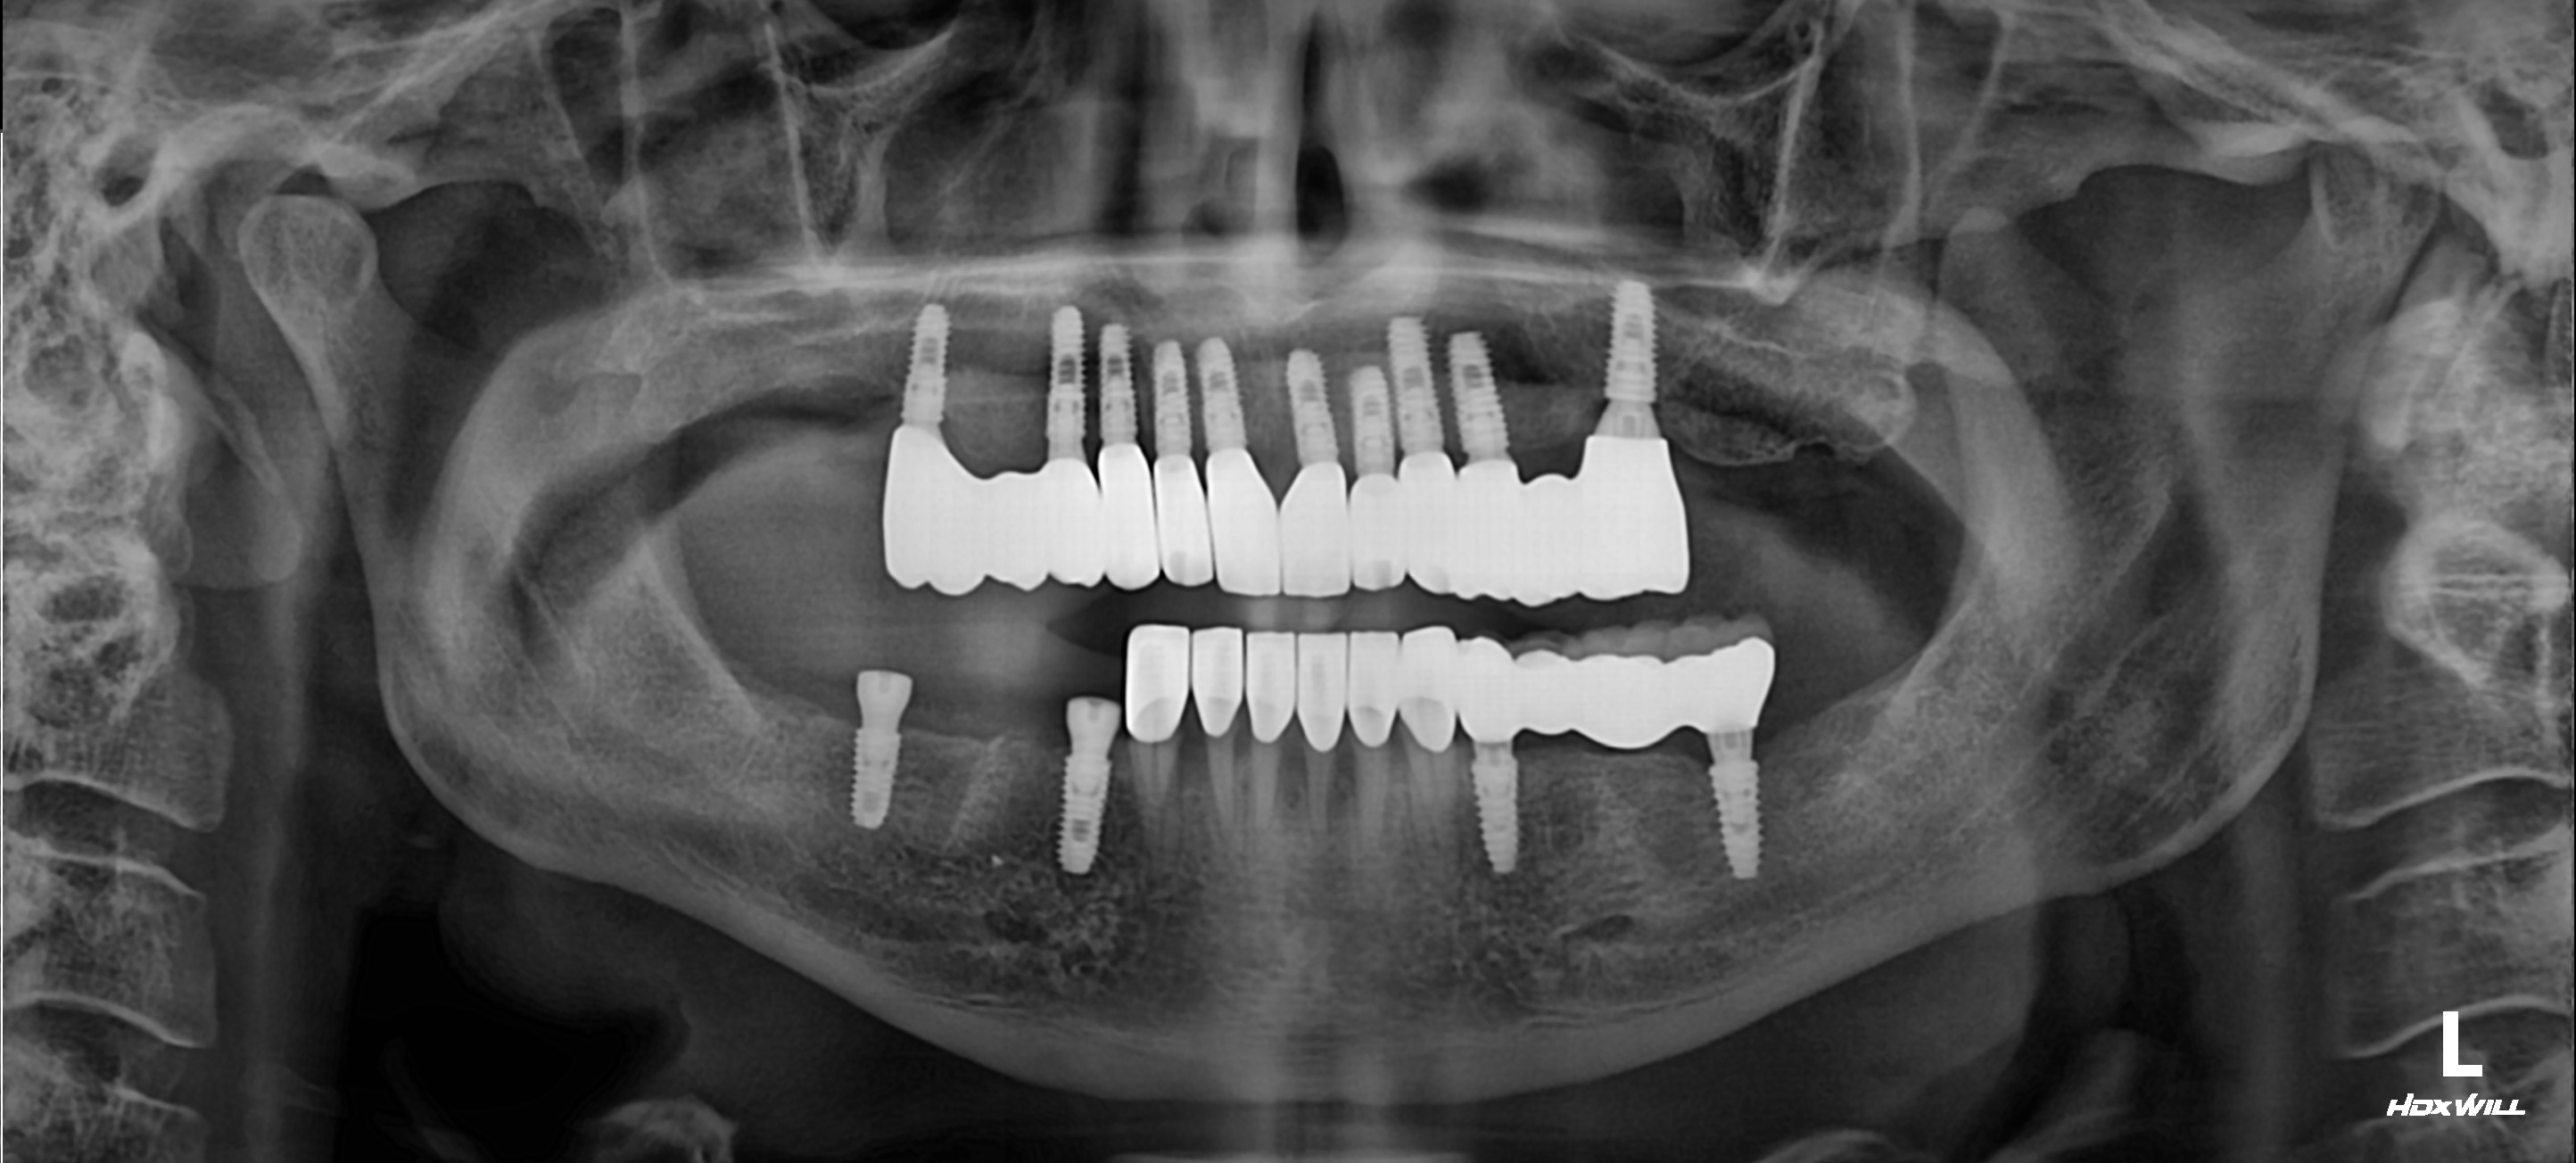

Имплантация зубов

Установлено 4 имплантанта Osstem во фронтальном участке верхней челюсти.

Протезирование выполнено коронками из оксида циркония с фиксацией на абатменты из оксида циркония.